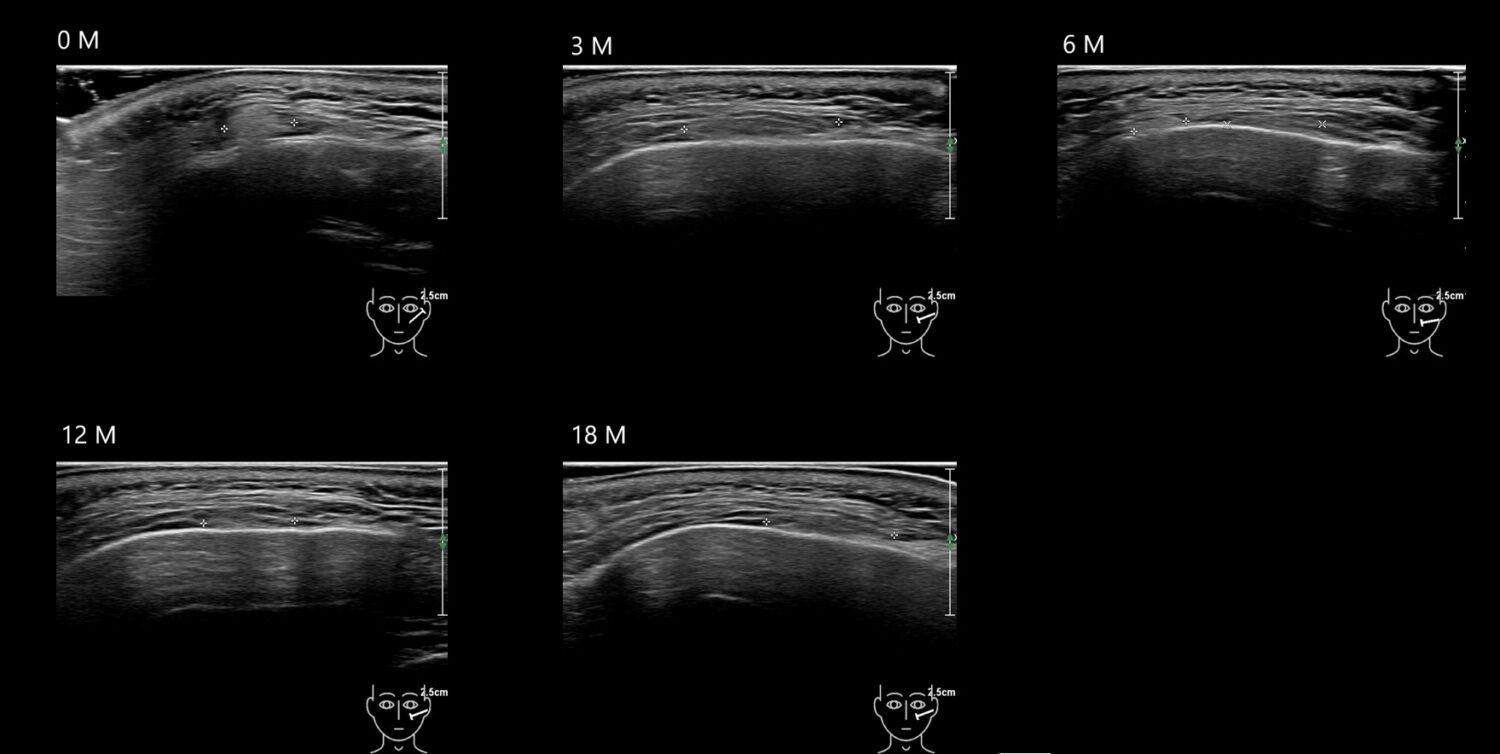

Fillers

Draw in the image on the right where the fillers are located. To check if your answer is correct, please click on the secondary image.